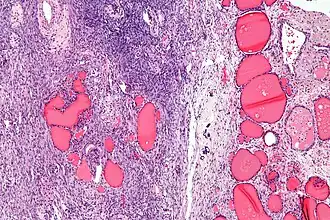

| Lâmina histológica de um struma ovarii. Pode-se observar folículos tireoideanos na direita, e estroma ovariano na esquerda. | |

Struma ovarii é um tumor do ovário, geralmente benigno e unilateral. Ele é uma variante de teratoma maduro, composta por mais de 50% de tecido tireoideano maduro. Corresponde a cerca de 1% de todos tumores de ovário e 2,7% dos teratomas maduros.[1]